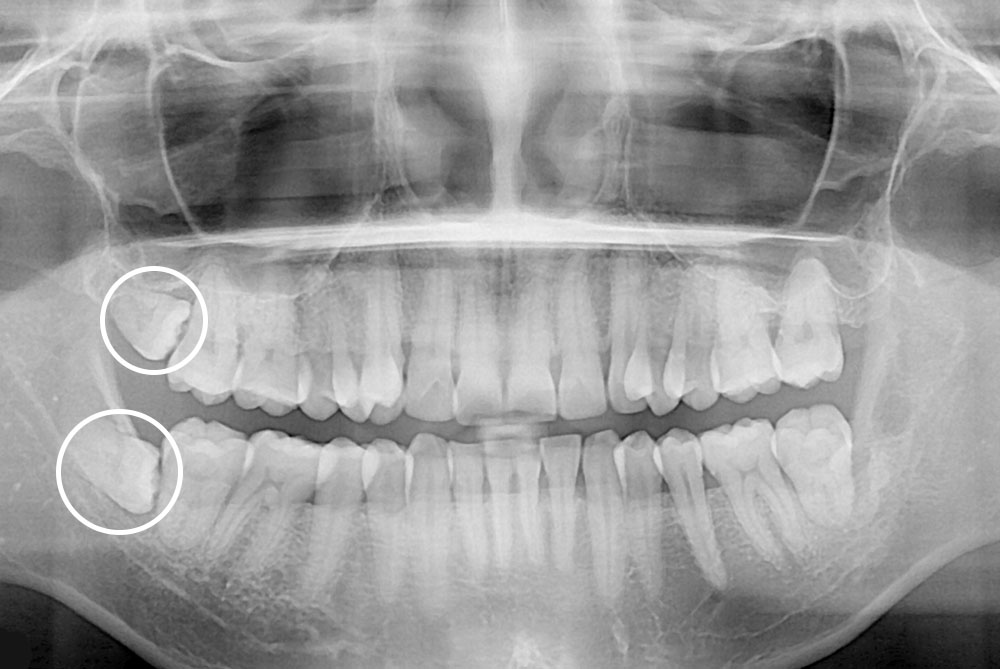

[사랑니] 매복 사랑니 발치

치료전 : 2019-05-07

세종치과는 구강악안면외과학 박사이신 원장님이 발치하는 치과입니다.